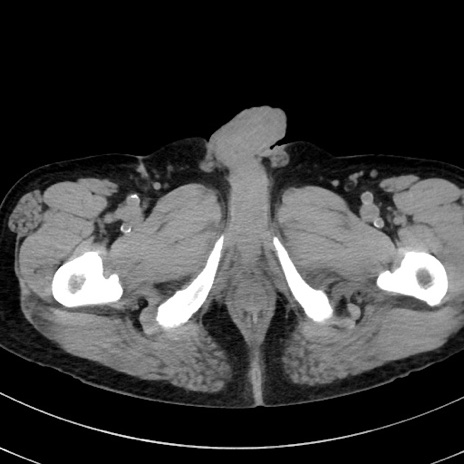

症例38(横断像)

【症例】70歳代 男性

【主訴】腹痛・嘔吐

【現病歴】昨晩より、嘔吐・腹痛あり。今朝になっても嘔吐あり。来院。

【既往歴】心臓バイパス手術、開腹胆摘、腸閉塞

【身体所見】BP 107/71mmHg、HR 116/min、腹部:平坦、軟、下腹部に軽度圧痛あり。反跳痛なし。

【データ】WBC 15100、CRP 0.32